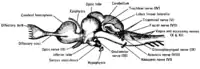

top; ventral bottom; lateral

The accessory nerve (XI) and hypoglossal nerve (XII) cannot be seen, as they are not always present in all vertebrates.

Cranial nerves are also present in other vertebrates. Other amniotes (non-amphibian tetrapods) have cranial nerves similar to those of humans. In anamniotes (fishes and amphibians), the accessory nerve (XI) and hypoglossal nerve (XII) do not exist, with the accessory nerve (XI) being an integral part of the vagus nerve (X); the hypoglossal nerve (XII) is represented by a variable number of spinal nerves emerging from vertebral segments fused into the occiput. These two nerves only became discrete nerves in the ancestors of amniotes.[28] The very small terminal nerve (nerve N or O) exists in humans but may not be functional. In other animals, it appears to be important to sexual receptivity based on perceptions of pheromones.[3][29]

The cranial nerves in the horse Ventral view of a sheep's brain. The exits of the various cranial nerves are marked with red.

Ventral view of a sheep's brain. The exits of the various cranial nerves are marked with red.